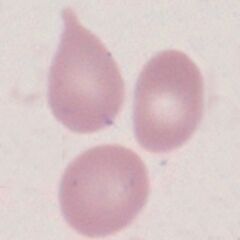

The abnormal cells have the shape of a tear drop.

Imaages: Sometimes described as having a “pinched top”, but the resemblance to a tear drop is probably the best description. Note that most often the cell is otherwise a normal erythrocyte with central pallor generally retained; but that other abnormal features (e.g. basophilic stippling, crenation, hypochromia) may all also occur. Features of infiltration or marrow hyperplasia may also be seen e.g. polychromasia, circulating nucleated red cells.